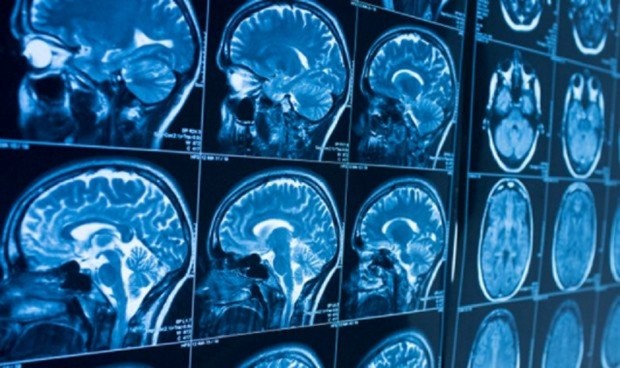

La resonancia magnética, detector de lesiones neuronales en deportistas

El fútbol le pasa factura a nuestro cerebro. Así lo ha descubierto un nuevo estudio que, mediante resonancia magnética, ha identificado las hiperintensidades de la materia blanca del cerebro asociadas a cambios neuroatológicos en atletas que practican deportes de contacto, como el balonpie.

La investigación, publicada online de 'Neurology', la revista médica de la Academia Americana de Neurología, también ha descubierto que las hiperintensidades de la sustancia blanca eran más comunes en los atletas que practicaban deportes de contacto durante más tiempo o que tenían más impactos en la cabeza durante sus carreras. Las hiperintensidades de la sustancia blanca son áreas que aparecen brillantes en las exploraciones de resonancia magnética (MRI) y son comunes en las personas a medida que envejecen y con condiciones médicas como la presión arterial alta.

"Nuestros resultados son emocionantes porque muestran que las hiperintensidades de la materia blanca podrían captar el daño a largo plazo en el cerebro de las personas que tienen un historial de impactos repetitivos en la cabeza, explica el autor del estudio, Michael Alosco, PhD, de la Facultad de Medicina de la Universidad de Boston (Estados Unidos). Las hiperintensidades de la materia blanca en la resonancia magnética pueden ser, en efecto, una herramienta eficaz para estudiar los efectos de los impactos repetitivos en la cabeza sobre la materia blanca del cerebro mientras el deportista sigue vivo".